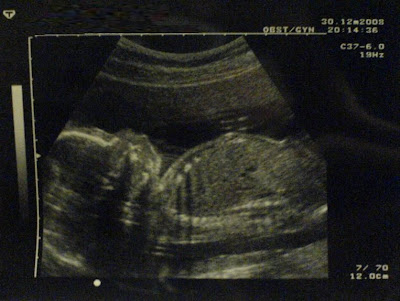

Mijn toekomstige neefje of nichtje

Oh Volk, wat lief! Hoe gaat het nu?

wow wat een mooie duidelijke zeg!

Nouja heel erg duidelijk istie niet maar je ziet wel de hele baby, hoofdje armpjes en voetjes... ipv alleen zo'n ronding wat dan het hoofd moet voorstellen.

Ik moest twee keer kijken, maar toen vond ik hem toch ook wel aardig duidelijk. Hoofdje links beneden, beentjes rechts boven, lijfje daartussen (dat is tenminste logisch ) en de armpjes ernaast (volgens mij zie je vooral de handjes).

Haha, ik zag er ook niets in Totdat ik Leonoor's post las. En nu zie ik het. Maar blijkbaar zijn echo's alleen goed te herkennen als je ze zelf wel eens gehad hebt ofzo, want ik zag er echt niets in

Ja hoor, links het hoofd, rechts de billen op de eerste, de 2e is een hand/arm en een been/voet (met een stukje van het bot in het bovenbeen) en de 3e is een doorsneede. Je ziet bijvoorbeeld de ribben (heel wit, met een zwarte slagschaduw) en het neusje. Je ziet in de schedelrand echt zo'n hobbeltje. Qua organen kan ik het zo niet zeggen, daar heb je eigenlijk de bewegingen en het dynamische van het onderzoek zelf voor nodig.

Maar dat is waarschijnlijk niet helemaal eerlijk aangezien ik mijn co-schap gynecologie al gedaan heb. Ik vind de echo's van baby's juist verreweg het makkelijkste eigenlijk Het zijn wel mooie plaatjes

De eerste is ook vaag, maar daar zie je wel duidelijk een vorm liggen, wat dus een baby zou kunnen zijn De tweede en derde zijn wel erg duidelijk. Daar zie ik meteen armen en benen (#2) en een hoofd met borst/buik (#3).

Die foto van Volk daarentegen is een grote witte vlek met daarin twee oogjes (de armen blijkbaar) en een mondkapje (het hoofd)